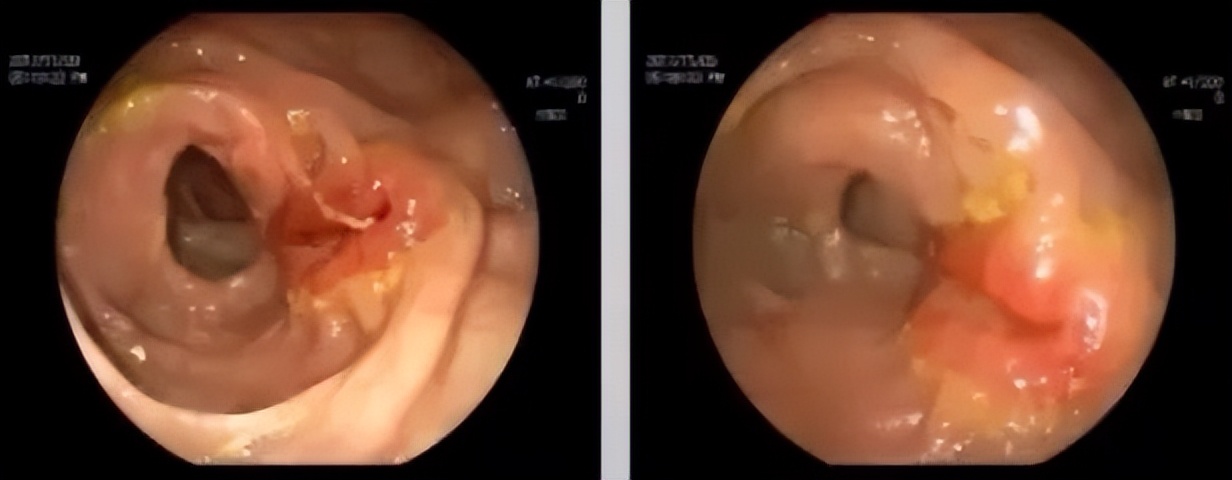

2017.11.9结肠镜

右半结肠-回肠吻合口附近见一溃疡面。

▲上:2016.12.21;下:2017.11.14。